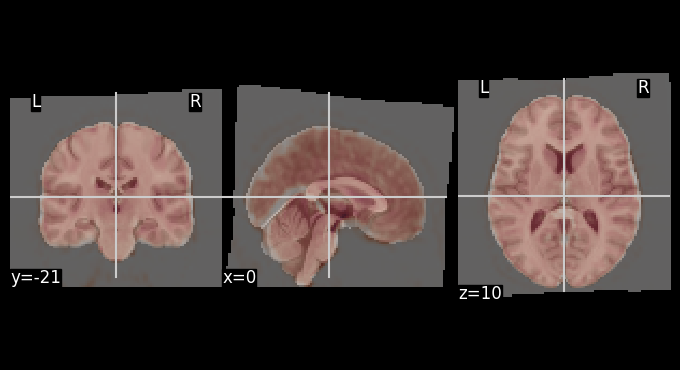

The mean BOLD image after motion correction was registered to the MNI template. The overlays below allows for visual inspection of alignment quality.

# Get mean BOLD image

mean_bold = image.mean_img(result_parallel.bold_preproc[0], copy_header=True)

# Overlay of the mean bold image on MNI background template

plotting.plot_stat_map(stat_map_img=mean_bold,

bg_img=template,

transparency=0.4,

colorbar=False)

<nilearn.plotting.displays._slicers.OrthoSlicer at 0x7f2fe916e510>